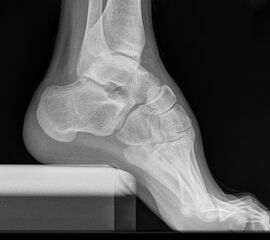

Kennzeichen des Röntgenbildes:

• Markieren der Tibiaachse mit Verlängerung nach distal.

• Der funktionelle Hebelarm des Kalkaneus errechnet sich aus der Distanz zwischen der Tibiaachse und dem am weitesten plantar gelegenen Punkt des Kalkaneus.

• Liegt der tiefste Punkt des Kalkaneus medial der Tibiaachse, handelt es sich um eine Varus-Stellung, liegt er lateral, um eine Valgus-Stellung.

• Norm: Auftrittspunkt 3,2 ± 8 mm medial der Tibiaachse 14.